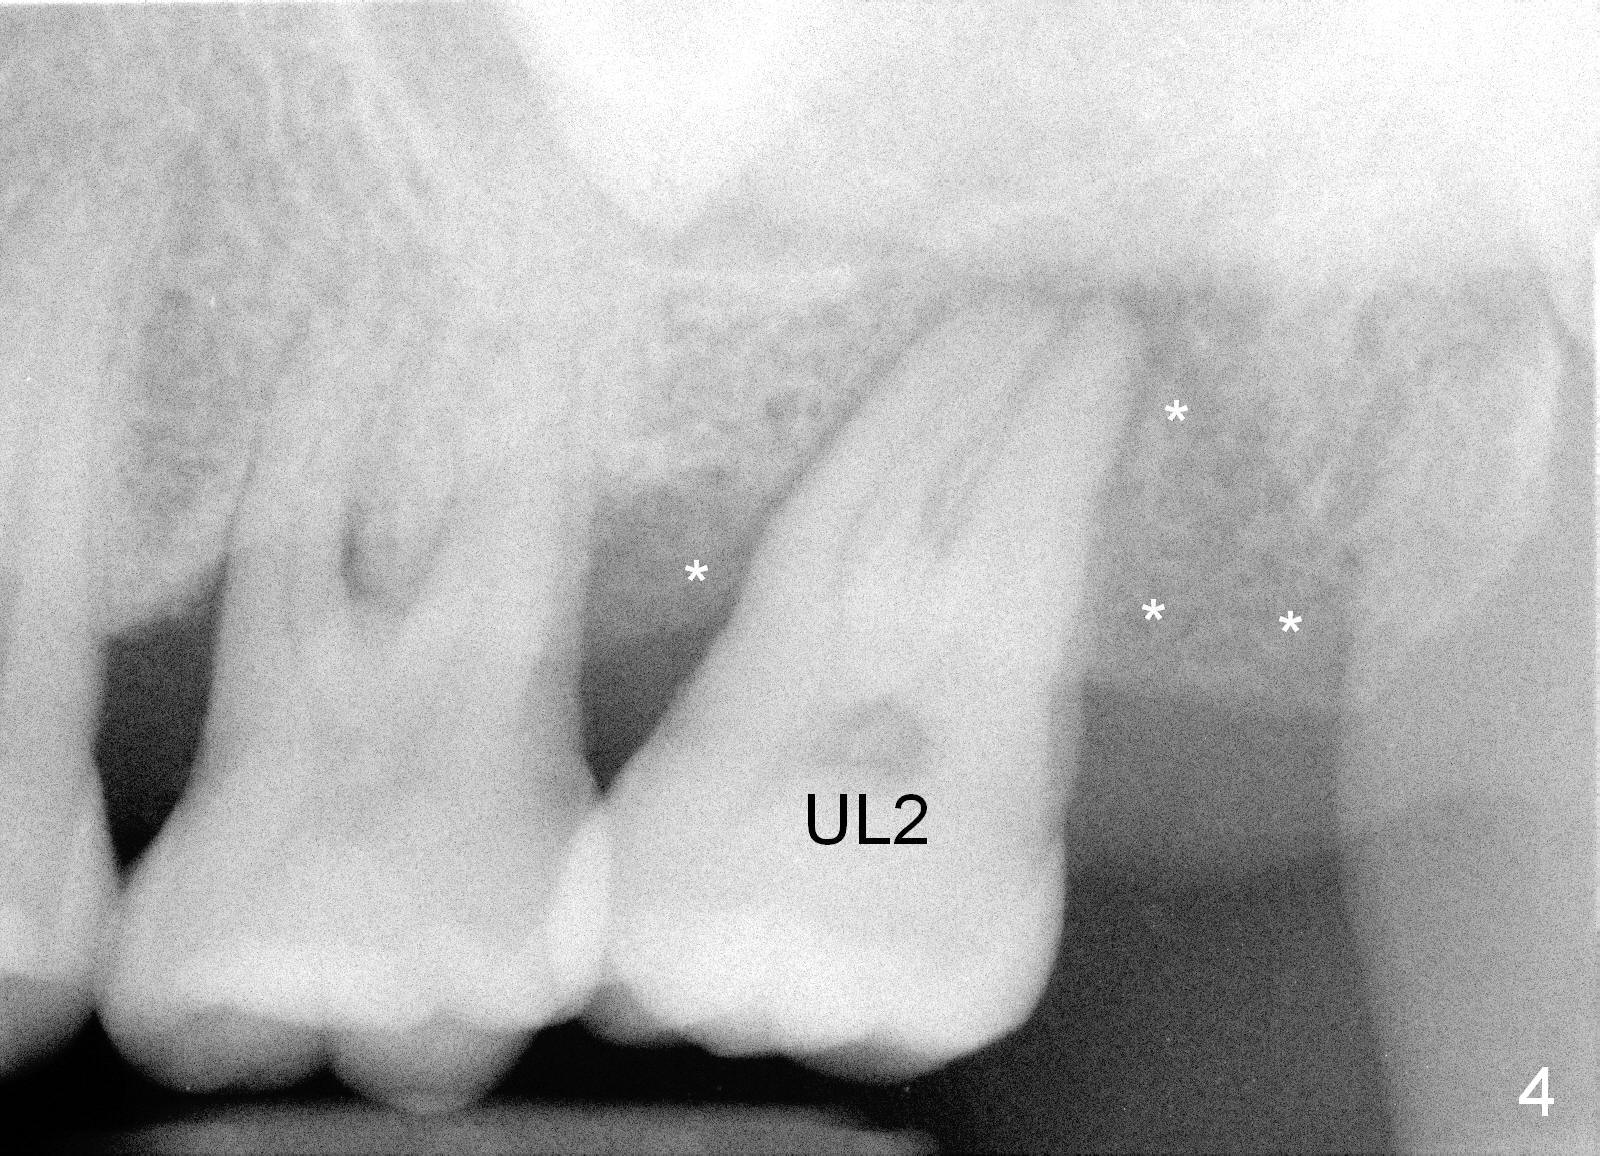

A 49-year-old lady is scared of dentistry. She presented with chronic periodontitis 7 years ago. The lower right 2nd molar had been missing (Fig.1 LR2), while the upper right 2nd molar shifted distally (arrow). Her chief complaint was mobility of #15 (Fig.2,4 UL2 with severe bone loss (*)). The tooth was extracted with expectation of return for implant placement in 6-8 weeks.

When she returns 7 years later, the tooth #2 has perio abscess with severe bone loss (Fig.3). She refuses to take antibiotic for infection control, but agrees to have immediate implant for #2 because of 1-staged surgery (Fig.5 I: 8x17 mm; A: abutment; P: bone powder (graft)). She is aware of delayed implants at the sites of #15 and 31 later. The bone height at the site of #15 reduces from 12 mm (Fig.4) to 7 mm (Fig.6) in 7 years.